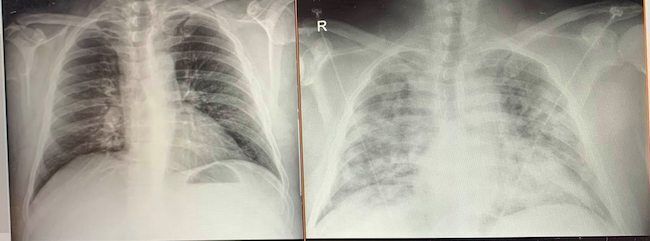

Aunque no se sea profesional sanitario, se puede observar la diferencia entre la radiografía de la izquierda de hace 3 días (normal) y la de la derecha ( de hoy, con una Neumonía bilateral). Desplegad la imagen y lo veréis mejor.